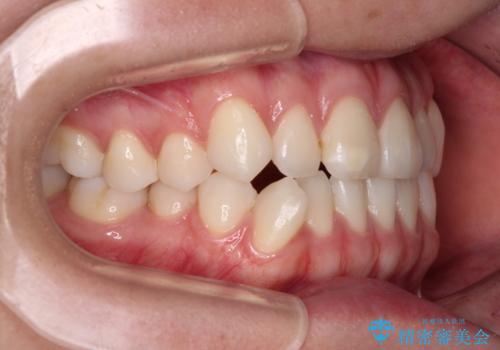

- 前歯のデコボコと奥歯の咬み合わせを気にして来院された患者様です。

右側の奥歯は、上が外側に転位した鋏状咬合を呈しており、前歯のデコボコ改善と並行して咬み合わせを改善していく必要がありました。